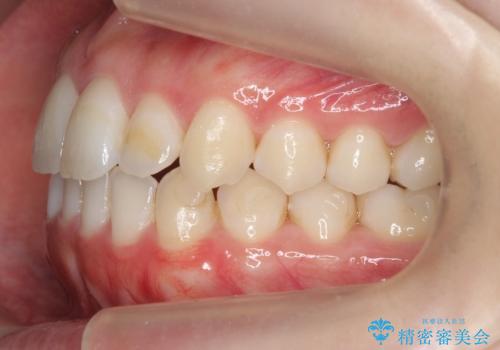

前歯のがたつきもしっかり治り、喜んでいただけました。

下の親知らずは虫歯になっていたため矯正前に抜歯しています。

- 前歯のがたつきが気になって来院。

下の歯のがたつきが上よりも多い状態でした。